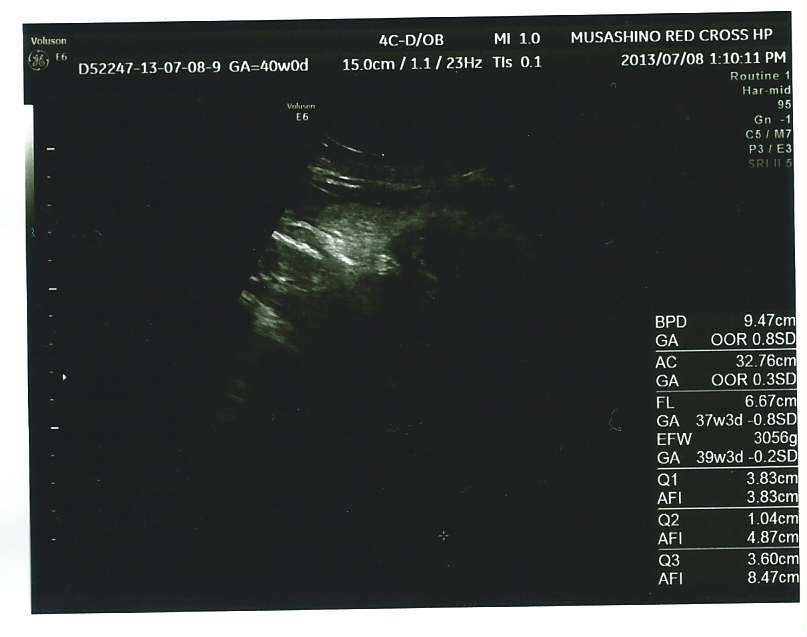

echo